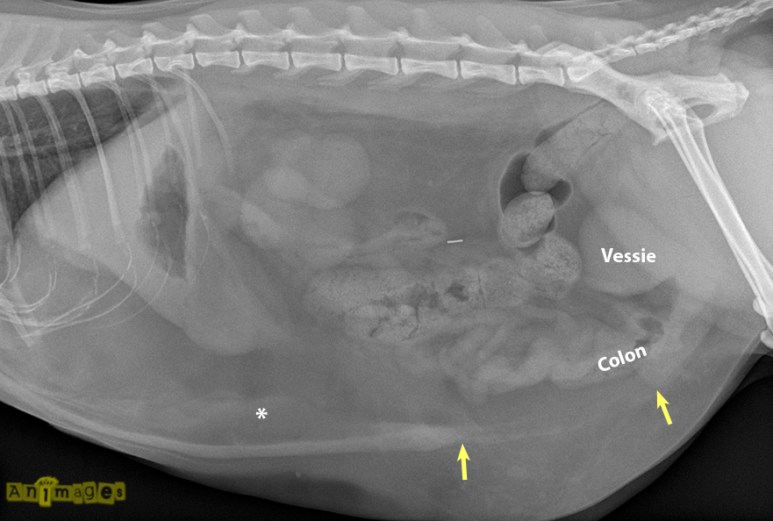

Au moment d’écrire cet article, un peu plus de 50% d’entres vous suspectiez autre chose que les premières réponses proposées… et vous n’aviez pas tort ! En effet, on remarque sur la vue latérale un large trou dans la paroi musculaire abdominale caudoventrale (délimité par les flèches jaunes), avec déplacement ventral de la vessie, du petit intestin et d’une portion du côlon. Les gras abdominaux (*) sont aussi hétérogènes et en partie opacifiés, en raison d’une inflammation ou congestion (oedème) de ceux-ci ou encore d’un épanchement péritonéal.

Sur la VD, une partie du petit intestin (flèches blanches) se retrouve déplacée latéralement au delà de la paroi abdominale caudolatérale droite (flèches jaunes), tout comme du gras abdominal. La paroi abdominale rupturée est d’ailleurs plus épaisse comme elle est rétractée et probablement oedématiée ou hémorrhagique. Notons également l’irrégularité des reins (surtout le rein gauche, RG) provoquée par des infarctions chroniques qui ont été confirmées à l’échographie.

Des matières fécales sont bien visibles dans le côlon (CA= côlon ascendant; CD= côlon descendant), mais pas suffisamment pour parler de constipation. Ceux qui ont vu un hémoabdomen avaient en partie raison, comme les changements aux gras pourraient y être associés. Pour ce qui est de la pyélonéphrite, une échographie aurait été nécessaire pour le confirmer. La vessie est déplacée, oui, mais non distendue et aucun calcul n’est visible pour suggérer une obstruction.